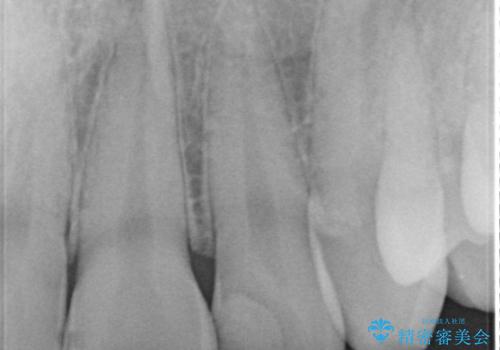

左上2番の大部分がプラスチックの材料で治療されていました。そのプラスチックの材料が劣化して変色し虫歯になっている状態でした。なので古いプラスチックの材料を全て除去し、その下の虫歯を取った後、オールセラミッククラウンで治療を行いました。オールセラミッククラウンを装着する前に当院にてホワイトニングを行いました。